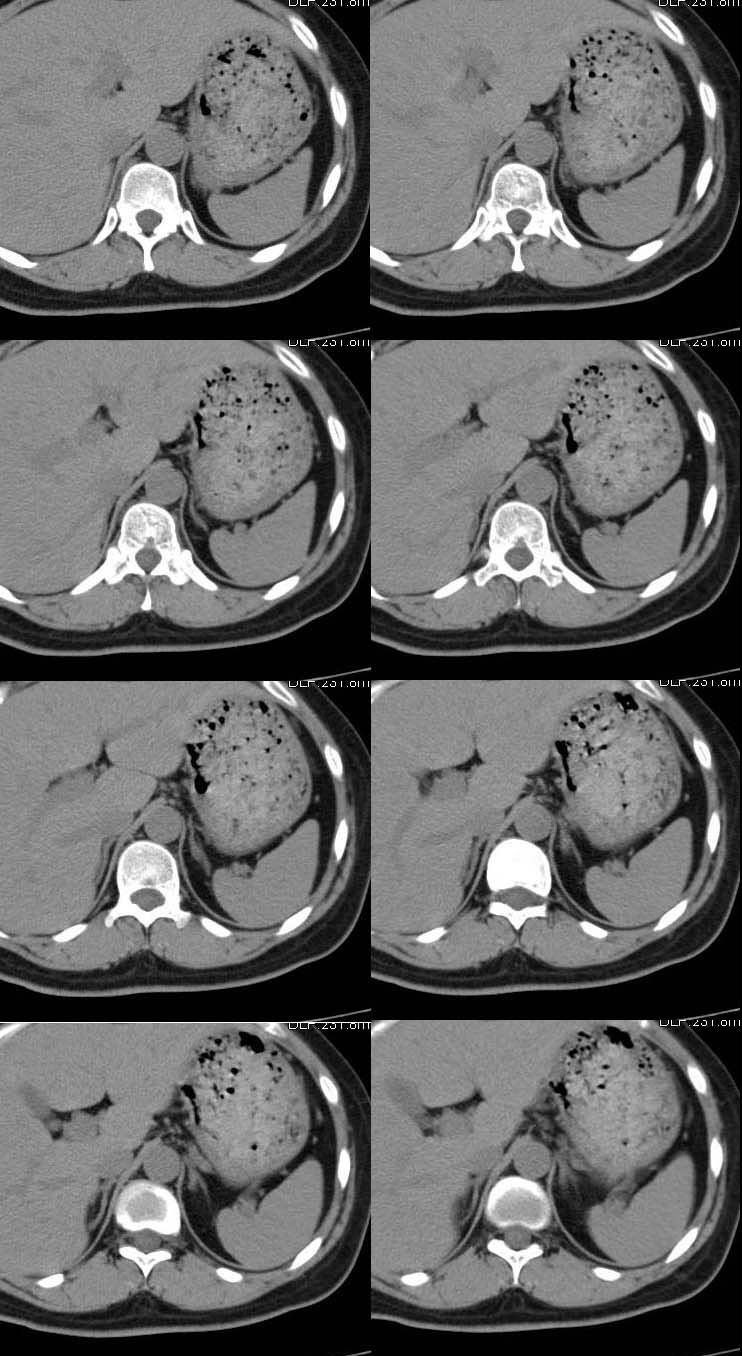

女,40岁,高血压病史,在外院ct增强扫描无异常强化,查激素水平去甲肾上腺素1100(正常<600)

ct平扫示左侧肾上腺内侧肢相对增粗,并似有一结节影.我考虑左侧肾上腺增生,大家意见?[